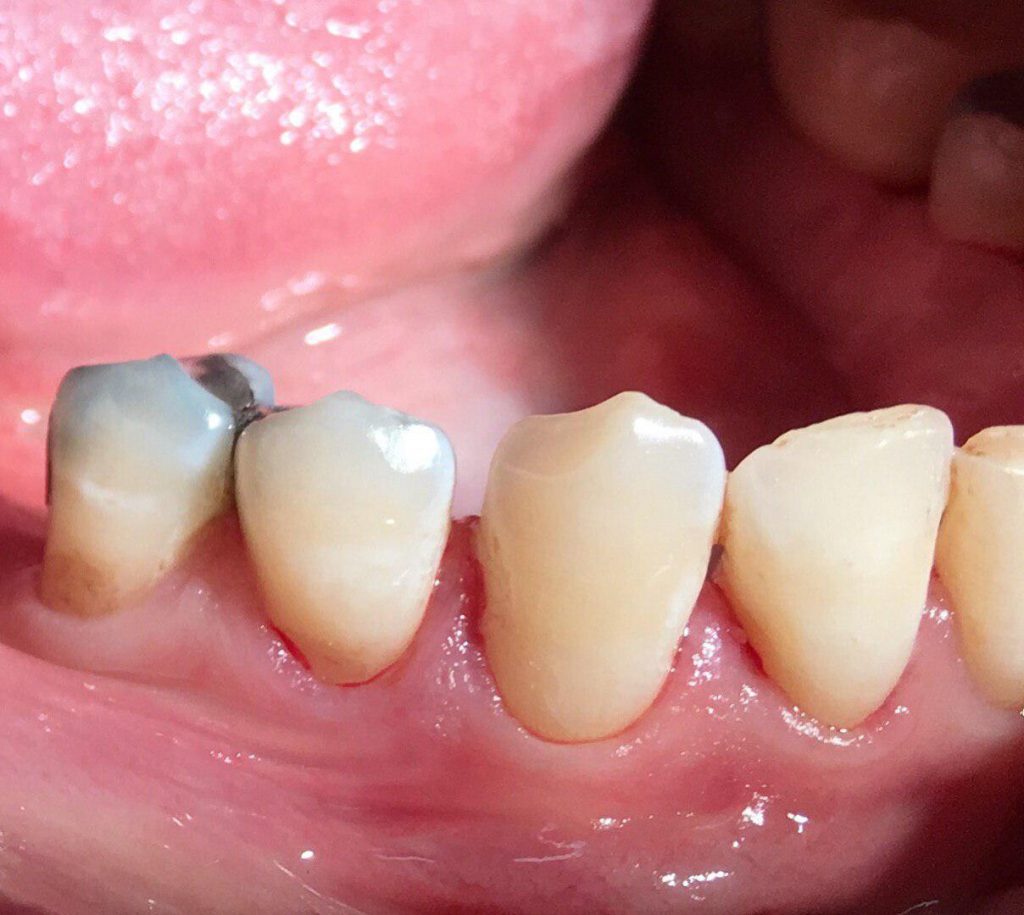

جراحی افزايش طول تاج جهت آماده سازی دندانها برای ترمیم و گذاشتن روکش

جراحی زیبایی لثه جهت بهبود شکل و اندازه دندانها حین لبخند زدن